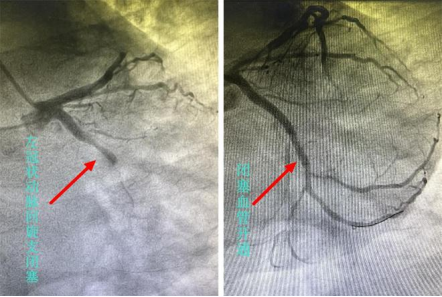

杨先生被送到常德一医胸痛中心,10分钟内,急诊科医护人员完善心电图、心肌酶谱等检查,心电图提示ST段抬高,心血管内科医生会诊后立即将杨先生送到导管室手术。常德一医心血管内科副主任郭宁为杨先生进行心脏冠状动脉造影,造影提示回旋支近端完全闭塞,随后通过支架植入开通血管。从送入导管室到血管开通,用时不到50分钟。

图左:11月25日,术中冠脉造影显示,杨先生的左冠状动脉回旋支闭塞。图右:冠脉支架植入术后,闭塞血管开通。